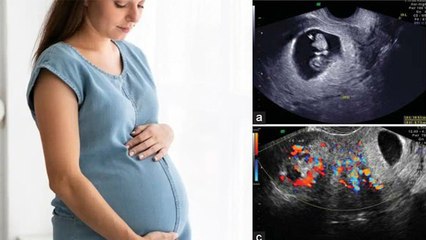

Megan Fox has revealed she suffered an ectopic pregnancy with someone she didn't love.